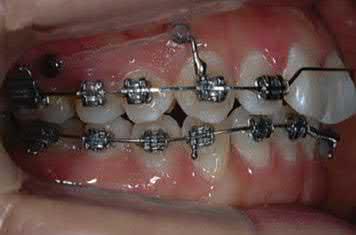

Figure 1.2  Class II correction with a double J retractor [10]. (a) Initial examination indicated a Class II Division 1 malocclusion with anterior crowding. (b) Schematic illustration shows a double J retractor and palatal TADs: palatal TADs (1, 2); anterior lever arm hooks (3); posterior lever arm hooks (4). (c) A double J retractor was connected to the TADs with elastomeric chains to achieve bodily translation. (d) Anterior tooth tipping can be controlled by adjusting the extension line of the force. (e) Maxillary anterior teeth were retracted and the extraction spaces were completely closed. (f) Maxillary anterior teeth were retracted and slightly tipped lingually. (g) Maxillary incisors were retracted after treatment. Source: Park et al. [10]. Reprinted with permission from Elsevier.

treatment outcomes with Class II malocclusion cases treated without extraction or severe bimaxillary protrusion with maxillary first premolar extractions [12, 13].